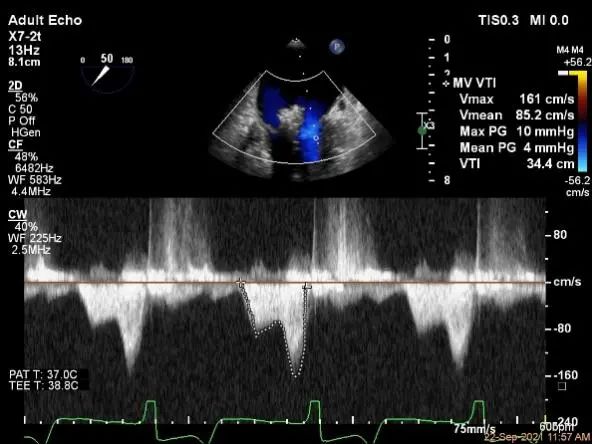

评估瓣口条件,平均跨瓣压差:2mmHg,决定在第一个夹子外侧下第二个夹子

评估瓣口条件,平均跨瓣压差:4mmHg